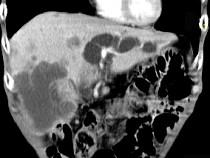

问题 男,49岁,右上腹痛半年,轻度黄疸,AFP阴性,CT检查如图,最可能的诊断为()

选项 A.原发性肝癌 B.胆管细胞癌 C.局灶性脂肪肝 D.肝脓肿 E.肝淋巴管瘤

答案 B